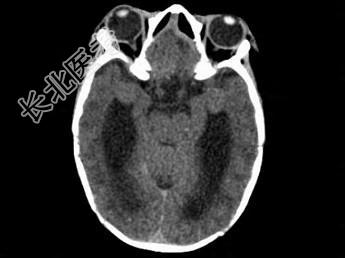

- 单项选择题两个月女婴,口咽部有一肿块, 行CT检查如图,请选择最可能的诊断 ( )

A、脑积水

B、胼胝体发育不全

C、透明隔囊肿

D、前脑无裂畸形

E、Dandy-Walker综合征